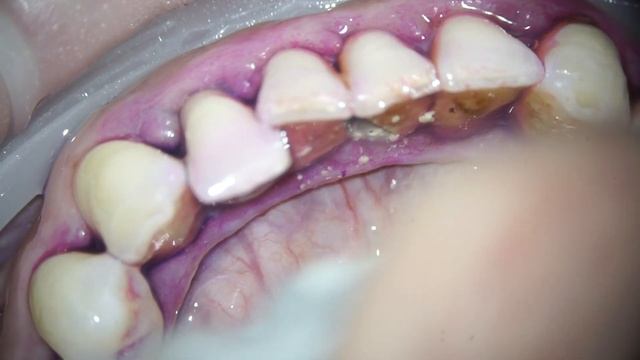

Удаление зуба мудрости / (Выпуск 15)

Удаление верхнего зуба мудрости на верхней челюсти